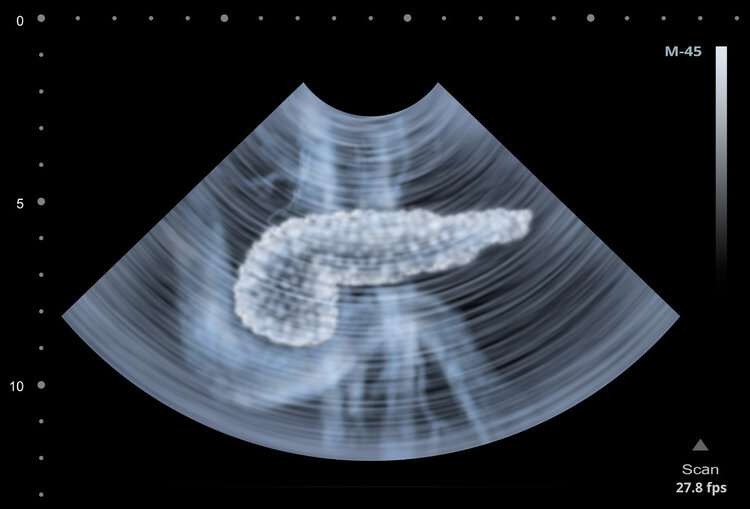

胰腺位于上腹部,在胃的后面,与肝、胆、脾等器官相邻,兼具内外分泌功能。因此,胰腺炎虽然发生在胰腺,但对身体的影响是多方面的,应引起重视。